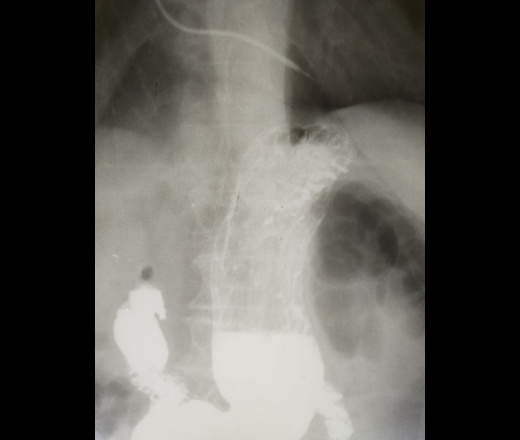

Здравствуйте! Женщина, 60 лет, жалобы на боли в эпигастрии, в анамнезе язва ДПК. Смущает участок на прямом снимке, который как будто выходит за пределы диафрагмы, но при этом вся картина как грыжа не выглядит. К сожалению, на скопии по техническим причинам не смотрели, только снимки в разных проекциях. С чем может быть связана такая картинка?

Вы все опишите как есть, отметьте, что по техническим причинам скопия была невыполнима ( да, думаю, что если и была бы доступна скопия едва ли она помогла бы, только надо было сделать снимок на живое с поворотом на правый бок после дачи глотка контраста( на пишеводно- желудочный переход). Порекомендуйте ФГС, не исключается формирующиеся грыжа пищеводного отверстия диафрагмы. Или повторить  исследование, когда будет работать скопия.

Высокое положение ампулы пищевода + увеличение угла Гиса = признаки ГПОД 1 ст., т.е. выхода брюшного отдела пищевода в грудную полость.